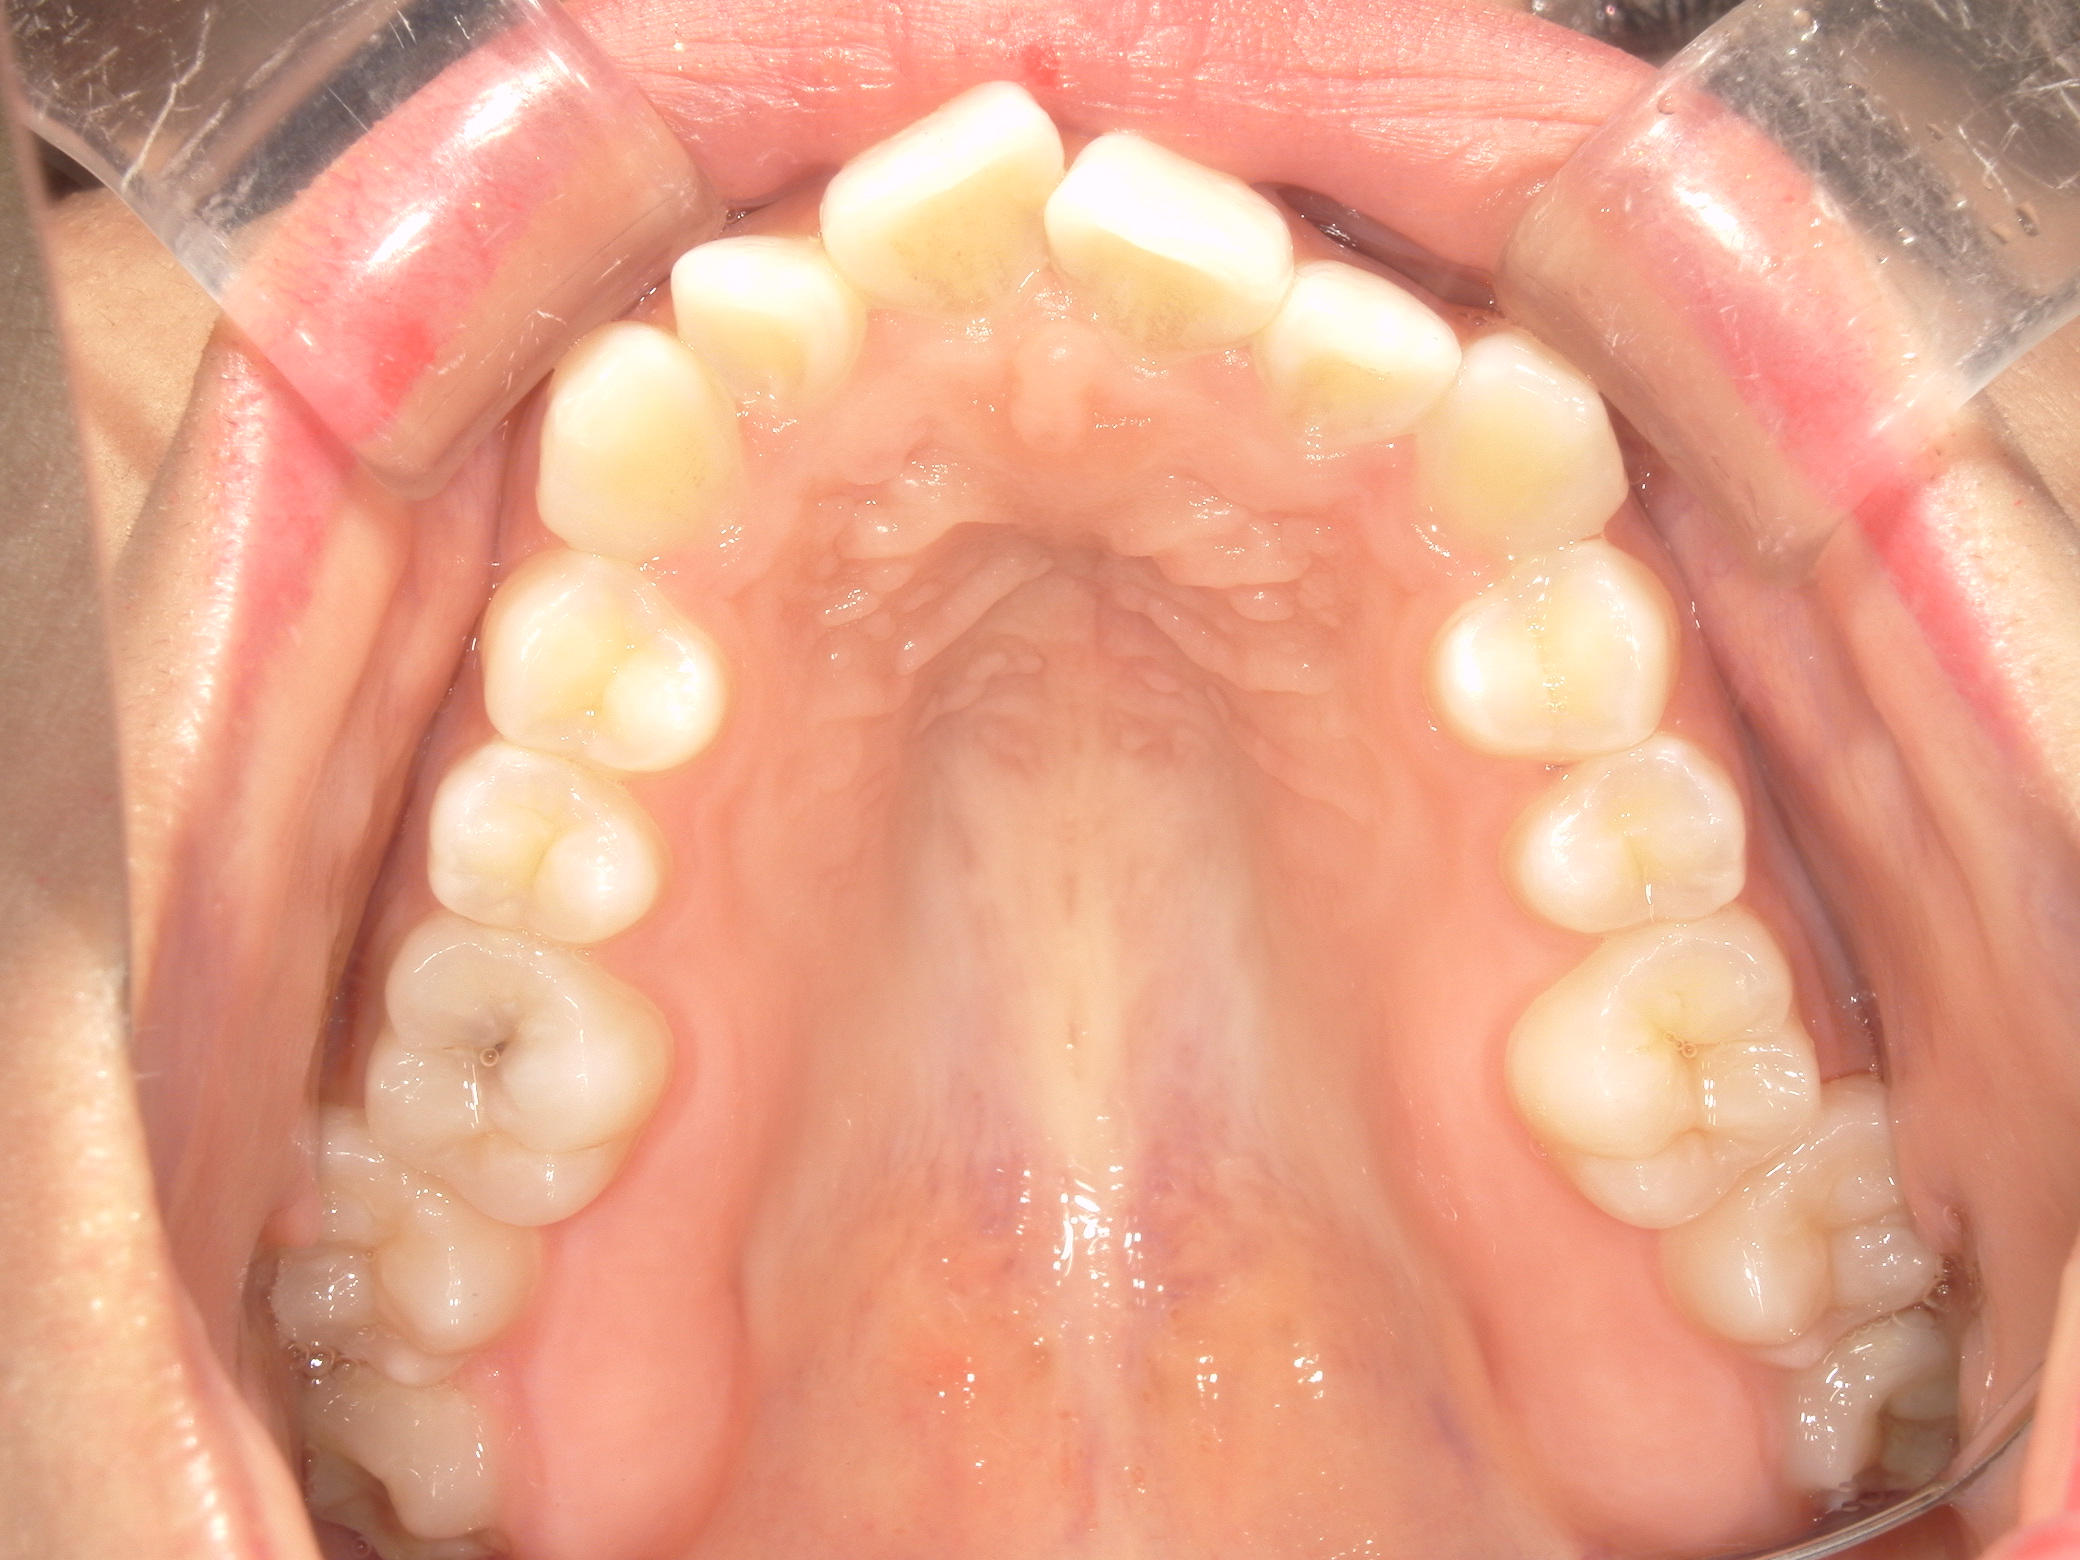

プチワイヤー矯正 症例(54)

主訴: 歯並びが気になる。

ミニインプラント(2本)、スライスカットを併用。

カテゴリー : ガタガタ(叢生)